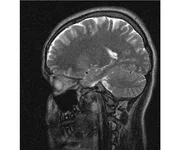

делал в обласной на siemense.В заключении выданом мне через 15мин.после мрт (легкая дегидрация)

Меня смутил факт выдачи заключения через 10мин(наверно они у них зарание напечатаные)я не медик.достаточно мимолётного взгляда на снимки?А вы видете на них гидроцефалию? Я лиш спросил куда идти с результатами томографии?и не хотел никого роздражать.

Я попросил взглянуть на снимки и сказать видна.ли на них гидроцефалия?или куда обратится за консультацией по этому вопросу?В мрт снимках наверно розбирается любой нервопатолог(я так предположил)

Я уже говорил, что независимо от того, есть на МРТ гидроцефалия или нет, лечиться тебе нужно только в том случае, если есть какие-либо проявления болезни, иначе на все эти анализы можешь забить... Но давай все-таки разберемся с томограммой.

Итак, с самого начала томограмма обозначала срез какого-либо органа на определенной глубине, позволяла заглянуть вовнутрь. При компьютерной томографии аппарат делает десятки срезов головного мозга в разных направлениях и из этого множества срезов он моделирует полноценное объемное изображение мозга в натуральную величину. Обрати внимание, компьютер работает не с этими миниатюрными изображениями, а с трехмерной моделью в масштабе 1:1. Эту модель вдоль и поперек анализирует суперсовременный компьютер, выполняющий миллионы операций в секунду. Только ***** может пытаться перепроверить компьютер, ведь человеку не хватит всей жизни чтобы проанализировать то, что компьютер с тобой сделал за 10 минут. Я хочу, чтобы ты это понял!

Ты разместл здесь несколько миниатюр и хочешь, чтобы врач по ним создал полноценное объемное изображение в натуральную величину, а потом осмотрел его со всех сторон и дал заключение? Но ведь это невозможно. Это просто насмешка над врачом, это издевательство над здравым смыслом. Принеси Букеру уменьшенный в 50 раз снимок зуба и спроси у него, в каком состоянии там корневые каналы. Или давай я дам тебе скрин со спутниковой карты города и попрошу тебя описать, какого цвета и какой модели запечатленная со спутника машина, какой у нее гос.номер, сколько в ней пассажиров, сколько из них мужчин и сколько женщин...

Надеюсь, ты понимаешь, что это невозможно. И воссоздать по приведенным тобой аватарам полную картину мозга тоже невозможно. Пойми, если уж называть вещи своими именами, то ты запостил полнейшую ***ню! Ты не хотел никого обидеть, ты ведь сам не ведал, что творил. Ты продемонстрировал полнейшую медицинскую безграмотность и полное невежество, но претензий к тебе нет. Ты ведь не один такой. Ты пожелал того, что сделать невозможно, и тут же у тебя нашлась сочувствующая, некая П., которую, по большому счету, надо бы послать в П., коль уж она считает, что врач должен тут сделать немедленно и бесплатно то, что делает немецкий компьютерный томограф ценой в миллионы долларов.